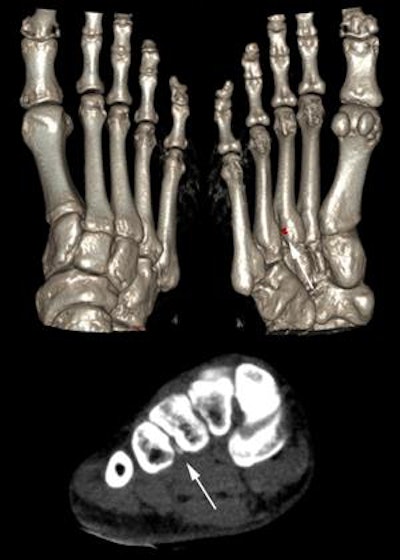

A 37-year-old patient presenting to the hospital with acute monoarthritis of the first metatarsophalangeal joint. Uric acid levels were elevated. The radiograph showed no changes, especially no erosions or gouty tophi. Doubt about the diagnosis of gout arose due to the young age of the patient. Dual-energy CT, however, depicted a small tophus at the third tarsometatarsal joint, which can easily be missed on conventional CT (arrows), confirming the diagnosis of tophaceous gout. Image courtesy of Dr. Torsten Diekhoff.

A 37-year-old patient presenting to the hospital with acute monoarthritis of the first metatarsophalangeal joint. Uric acid levels were elevated. The radiograph showed no changes, especially no erosions or gouty tophi. Doubt about the diagnosis of gout arose due to the young age of the patient. Dual-energy CT, however, depicted a small tophus at the third tarsometatarsal joint, which can easily be missed on conventional CT (arrows), confirming the diagnosis of tophaceous gout. Image courtesy of Dr. Torsten Diekhoff.To compare the imaging findings with the clinical presentation, the researchers retrospectively measured levels for serum uric acid, leucocytes, erythrocyte sedimentation rate, C-reactive protein (CRP), creatinine; a final diagnosis was made by referring rheumatologists. Based on the rheumatologist's final diagnosis, the patients were divided into a gout group and a control or "other diseases" group.